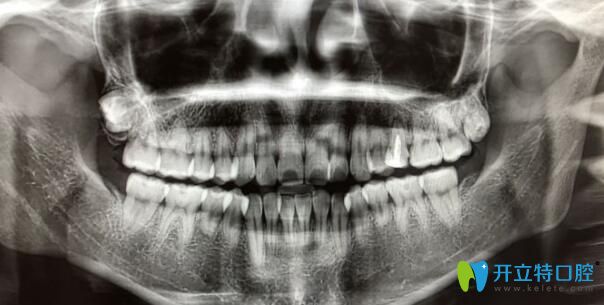

案例二:牙根短做正畸5個(gè)月自白

其實(shí)做正畸之前,我也非常擔(dān)心,但是變美的沖動(dòng)大于一切,所以在認(rèn)真的篩選了和醫(yī)生之后,我開始了我的正畸之旅。

牙根短做正畸5個(gè)月自白

我已經(jīng)戴牙套5個(gè)月了,下個(gè)月還要打種植釘,而且迄今為止都比較好。

牙根短做了牙齒矯正

到現(xiàn)在我還是不后悔。沒有覺得牙齒有松動(dòng)。為自己悄悄變美每天都很高興。